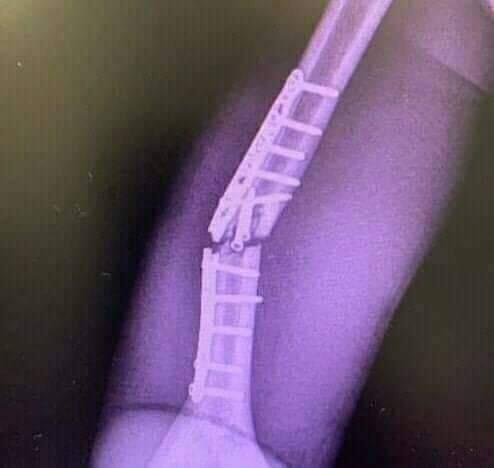

Jiah cederanya makin parah

Harusnya kmrn ga usah maksa turun dulu marc